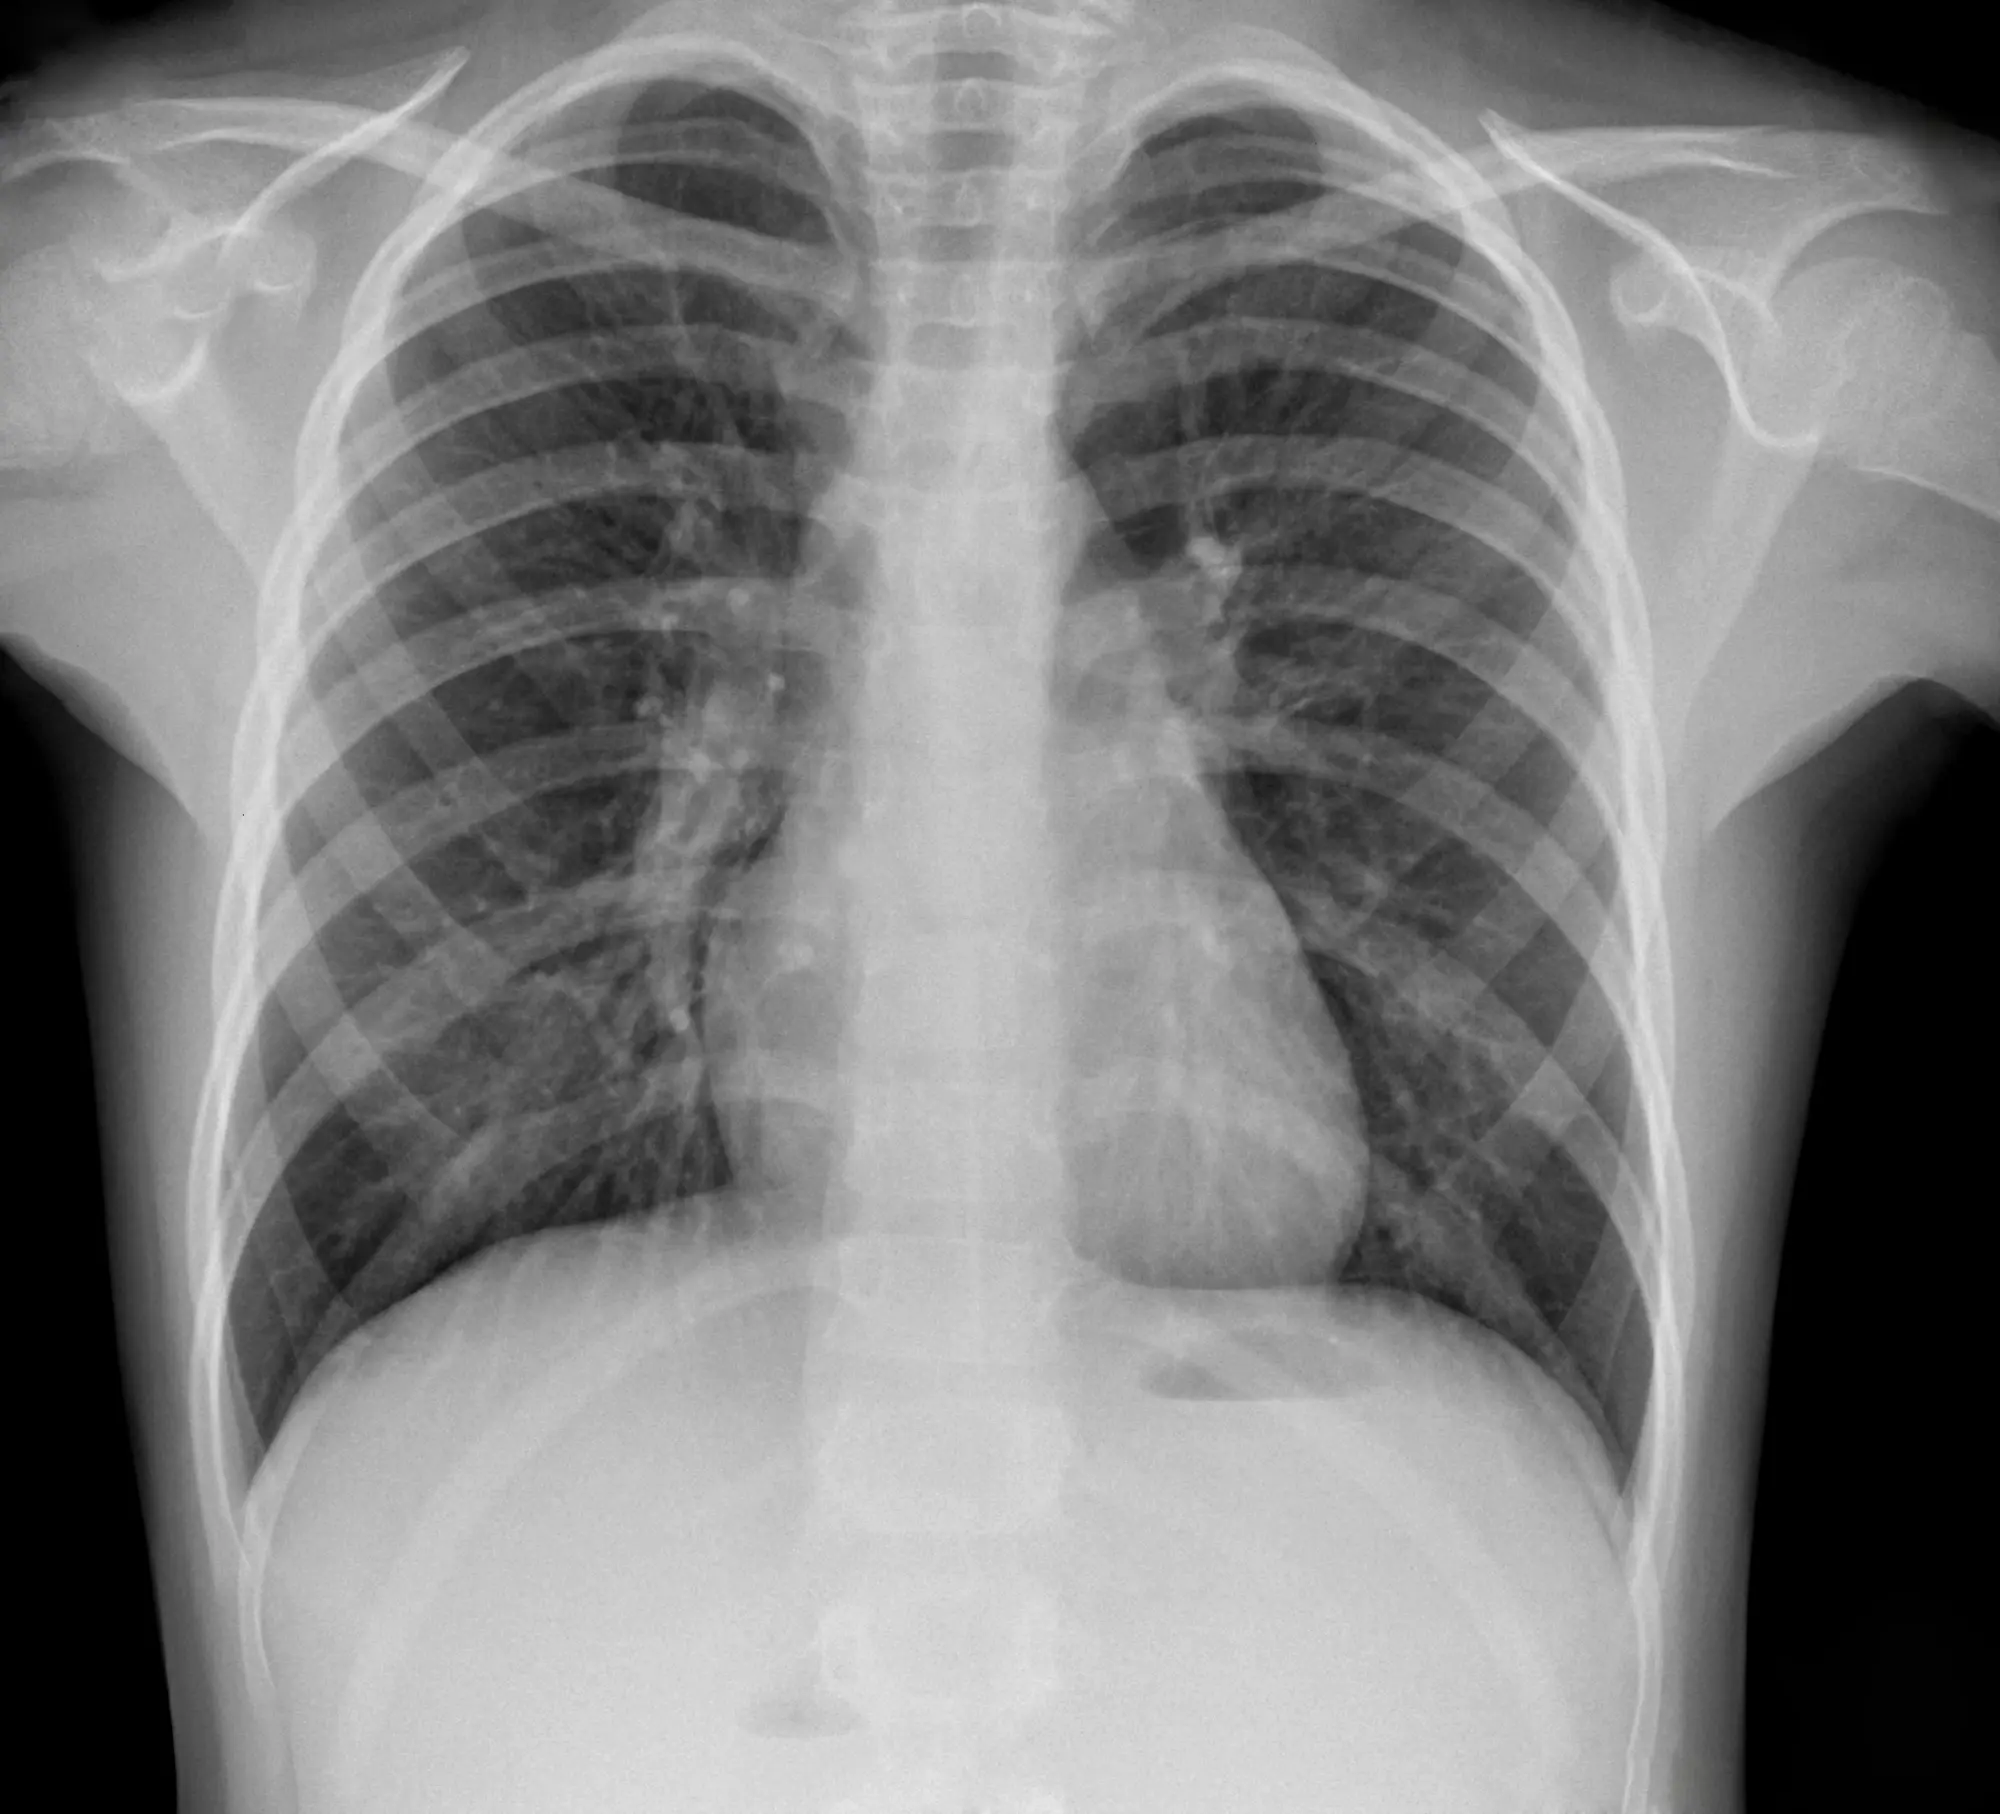

On commence à la cerner ! Si plus de 30.000 Marocains sont infectés chaque année par la tuberculose, les autorités sanitaires font le nécessaire pour éliminer cette maladie infectieuse, d’ici 2030.

Alors qu'au niveau mondial, la tuberculose est toujours la maladie infectieuse la plus meurtrière avec plus d'1,5 million de morts par an, "le Maroc a réduit de 33% le nombre des nouveaux cas de tuberculose, entre 1990 et 2018, estimant ainsi le taux de succès de traitement de la maladie à 86%", a expliqué le ministre de la Santé, Anas Doukkali, à l'occasion du lancement d'un Centre de diagnostic de la tuberculose et des maladies respiratoires à Rabat.

Le taux des décès diminue

Dans une déclaration à la MAP, le ministre a indiqué que le taux de diagnostic de la maladie a dépassé les 85%, alors que celui des décès a diminué de 68%. Des résultats qui s'expliquent sans doute par le lancement, il y a 18 mois, du plan stratégique national de lutte contre la tuberculose 2018-2021. Ce dernier vise à porter le taux de dépistage de la tuberculose à 90% et passer le taux d'efficacité du traitement à plus de 90%, tout en réduisant le nombre décès.